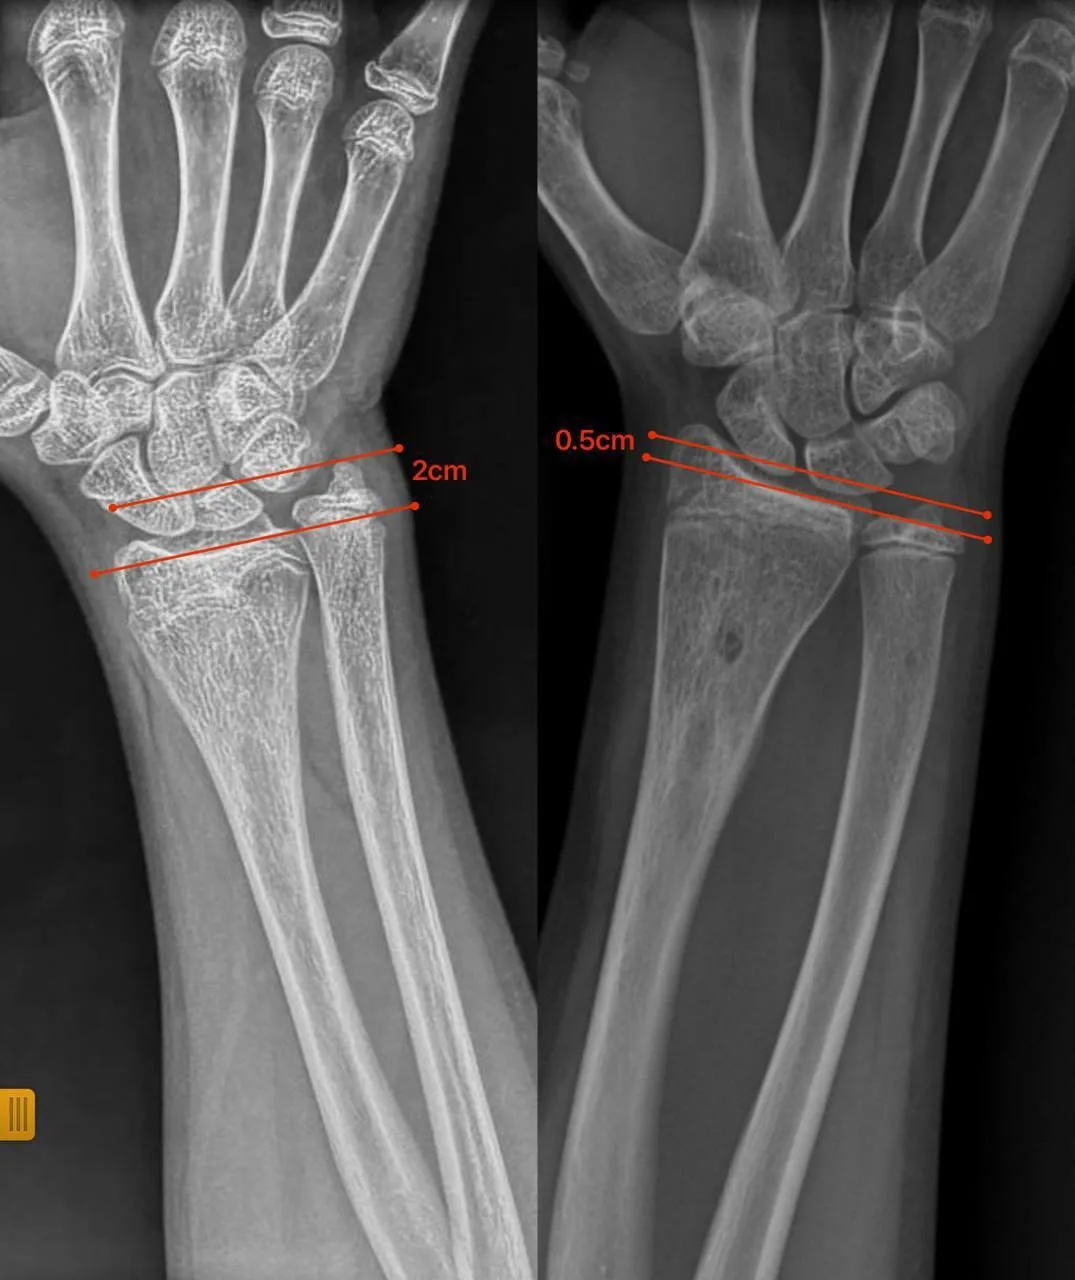

Нещодавно до відділення звернулися батьки 12-річної дівчинки з іншої області з післятравматичною деформацією кісток передпліччя. Лікарі виявили, що ріст кістки порушився через утворення кісткового мостика, який заважав росту кістки та деформував її.

Під час операції спеціалісти видалили кістковий місток під контролем ендоскопа. Такий малотравматичний підхід дозволив відновити природний ріст кістки без складних остеотомій чи встановлення металоконструкцій.

Через сім місяців передпліччя дівчинки повністю відновило форму, ріст кістки нормалізувався, а рухливість кінцівки збережена.